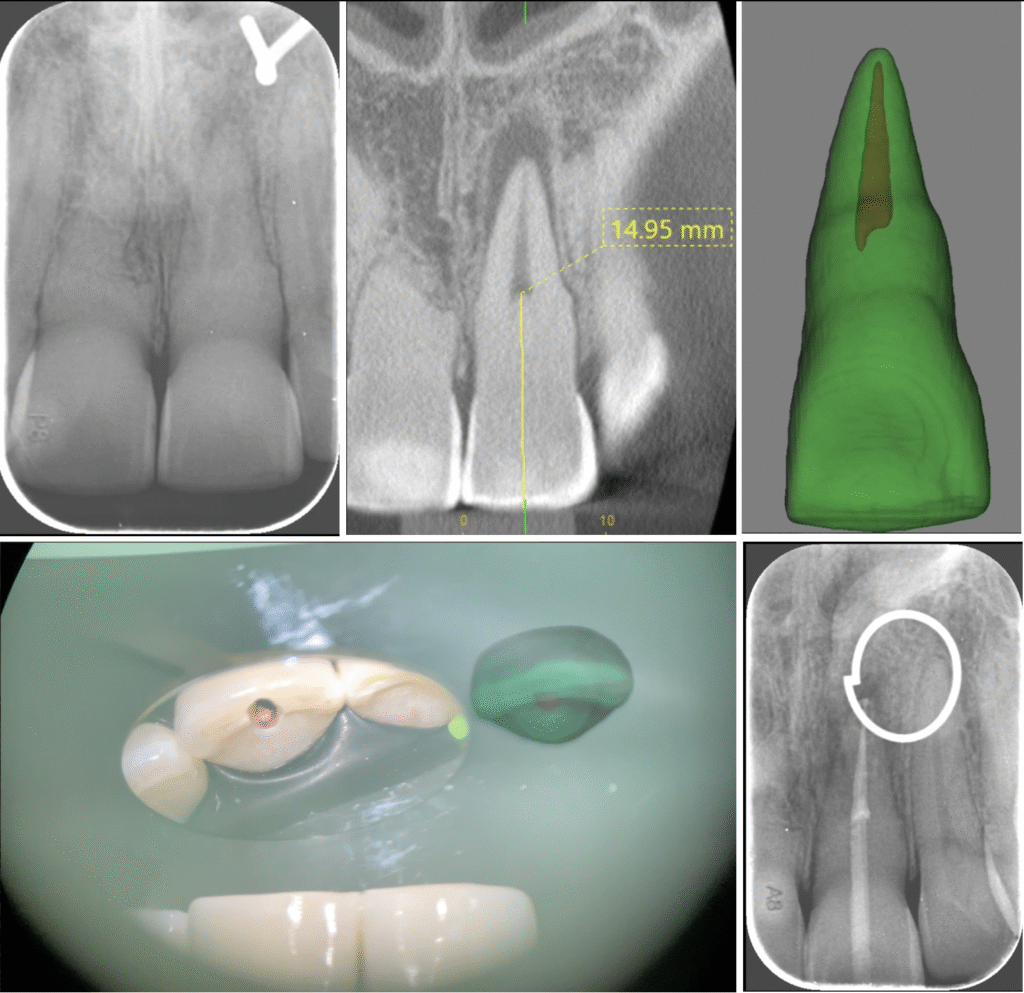

Case History: A 56 year old male patient was referred for evaluation of tooth #7 and #8. He is asymptomatic, but his general dentist referred him after observing a buccal sinus tract over tooth #7.

HPI: The patient reports RCT #8 and crowns on #8 and #9 following a bike accident over 20 years ago. The teeth have been asymptomatic ever since, but the patient reports a "bump" in the gums developing on and off over the past year.

Radiographic evaluation: Periapical radiographs of the maxillary anterior teeth show existing PFM crowns on teeth #8 and #9 with previous root canal therapy of tooth of #8 with a large post. The obturation material is lacking in density in the apical portion of #8. Both #7 and #8 lack a continuous lamina dura and a large periapical radiolucency is present compassing both roots. The severe lack of density within the radiolucency indicates a through-and-through lesion.

A limited FOV CBCT was exposed revealing an area of low density (14x12x10mm in dimension) encompassing the root apices of #7 and #8. Significant erosion of the buccal and palatal cortical plates is evident. The alveolar bone around #7 and #8 is intact circumferentially.

Clinical evaluation: Probing depths 2-3mm across all maxillary anterior teeth. None are tender to percussion or palpation. Tooth #7 responded positively to cold testing.

Tooth #7 has class 1 mobility and #8 has class 2 mobility. A buccal sinus tract is present in the attached gingiva above #7. The #8 and #9 PFM crowns are intact with clinically sealed margins.

Diagnosis:

Tooth #7 normal pulp with asymptomatic apical periodontitis

Tooth #8 previously treated with a chronic apical abscess.